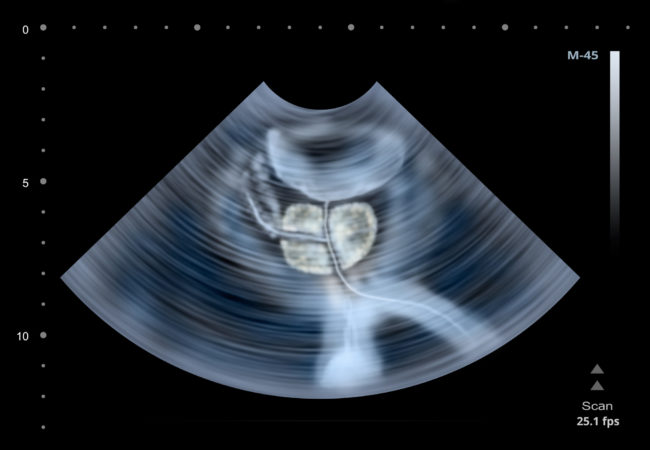

Фото УЗИ простаты у мужчин можно рассмотреть ниже.

На фото после проведения обследования ультразвуком всегда можно рассмотреть аденому. Если опухоль доброкачественного характера определить рано, то у пациента высок шанс получить благоприятный прогноз и вылечить болезнь без проведения оперативного вмешательства.

Врач при изучении фото ультразвукового исследования получает возможность не только узнать, в каком участке органа конкретно находится новообразование, но также понять его масштаб. Также дополнительно можно определить наличие камней в простате.

Результаты обследования будут получены сразу после окончания процедуры. На протяжении исследования врач внимательно просматривает видео с экрана монитора и делает вывод о наличии патологии либо ее отсутствии, особое внимание он обращает на существующие нормы размера органа. Правильная расшифровка данных с экрана монитора нуждается в профессионализме и опытности врача. Фото, как делают УЗИ простаты у мужчин, представлено в статье.

Фото, как делают УЗИ простаты у мужчин, находится ниже.